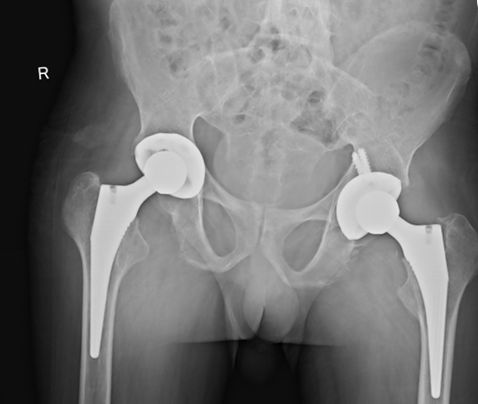

例2:29岁男性,AS患者,双髋、双膝关节疼痛伴活动受限6年

例2:行双髋、双膝关节置换后疼痛明显缓解、恢复行走功能